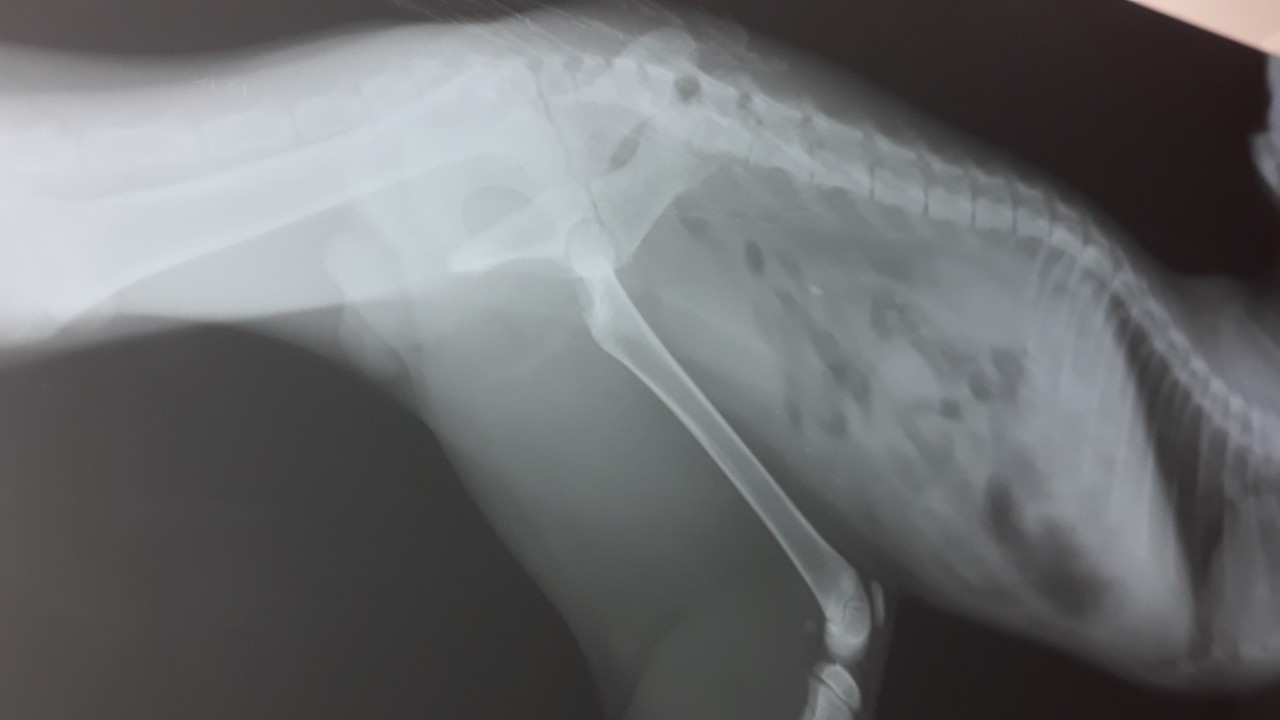

Помогите спасти котёнка ,его выбросили с 9-го этажа, у него перелом 3-х лапок,перелом таза и забита грудная клетка...!!!!((((

Он лежит на реабилитации в клинике на Сахарова 36...Не безразличные люди собрали уже 1000 гривен.Операция стоит около 3 тыс. гривен.